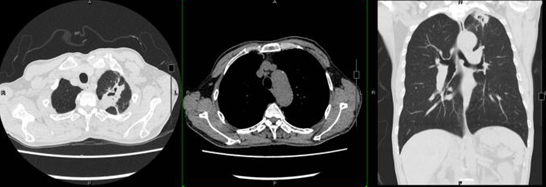

患者1个月前(2018年3月31日)因胸痛至我院就诊,诊断为急性肺动脉血栓栓塞症(图1A),4月8日复查胸部CT血栓吸收不明显(图1B),遂于4月11日予阿替普酶50 mg溶栓治疗,后予华法林抗凝治疗,4月16日复查胸部CT示血栓吸收,好转后出院(图1C)

图1  患者胸部CT

注:A为3月31日患者双肺动脉主干及分支多发肺栓塞;B为4月8日患者双下肺动脉干及右中叶动脉栓塞较前稍有吸收;C为4月16日双下肺动脉干及分支栓塞较前吸收